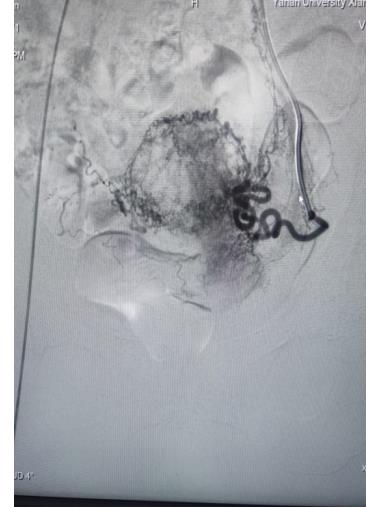

左侧子宫动脉栓塞前后对照